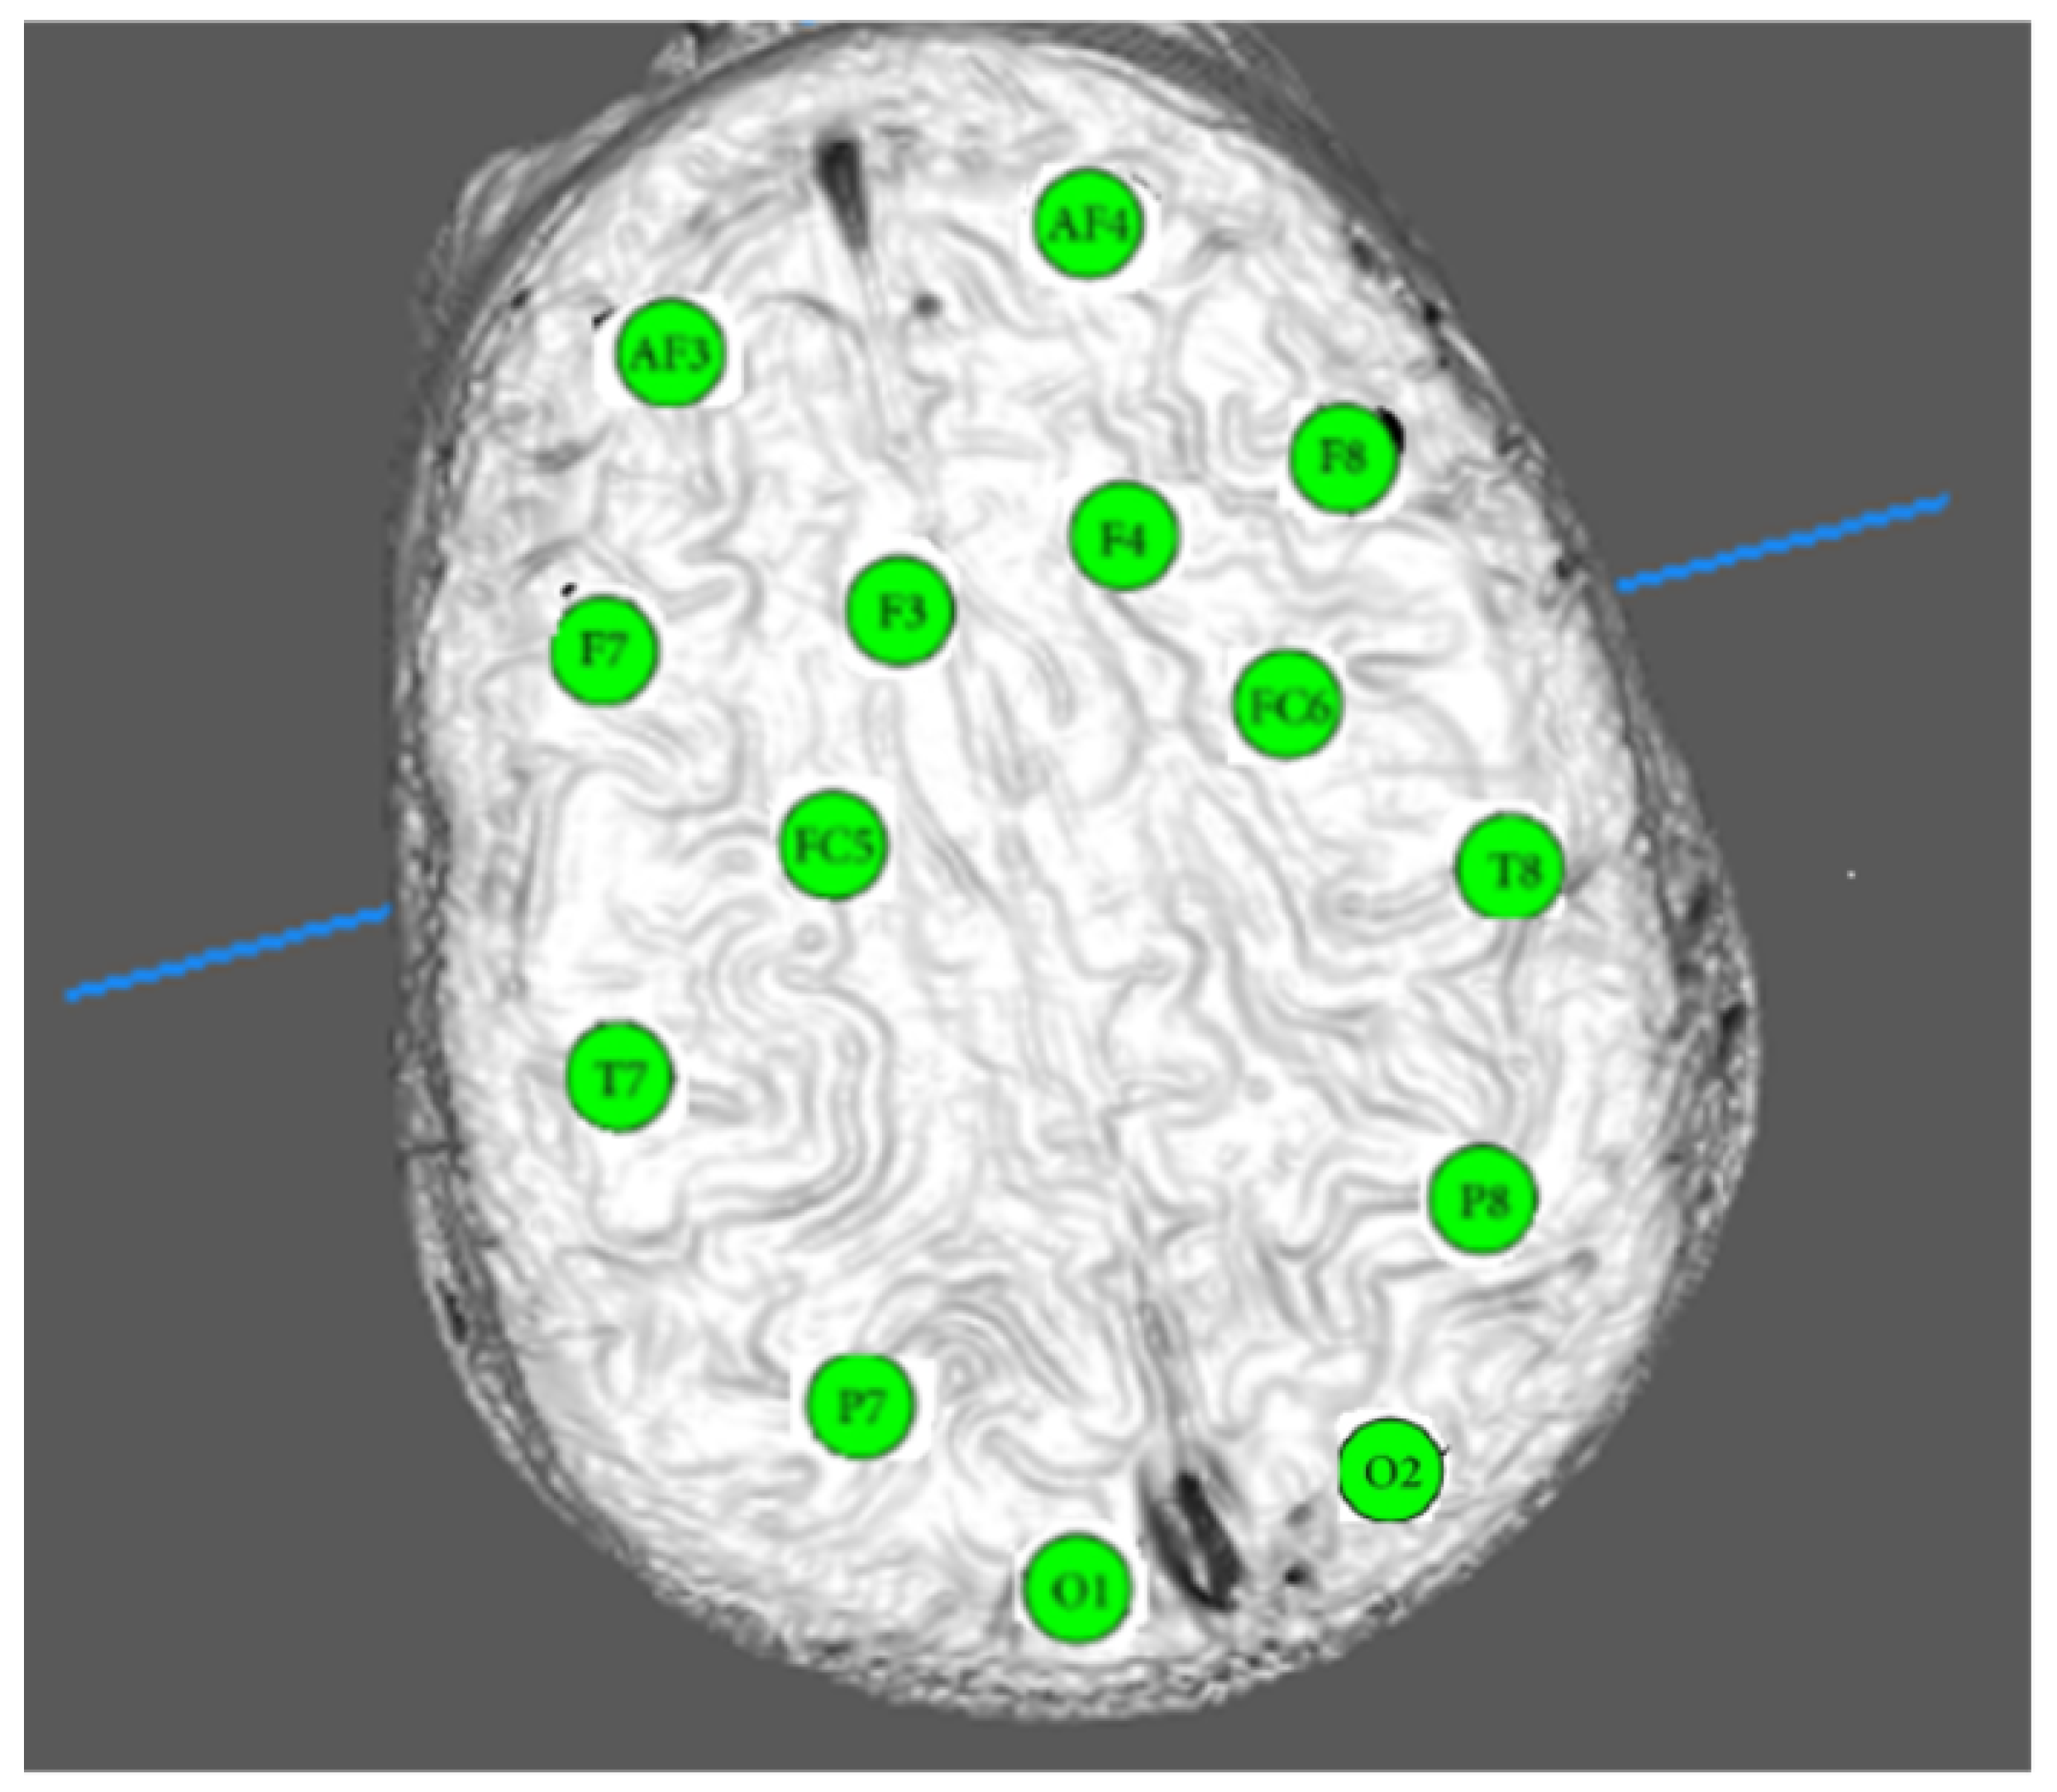

- A DBMSE index was obtained for each subject per EEG channel, indicating the most affected areas of the brain during such situations.